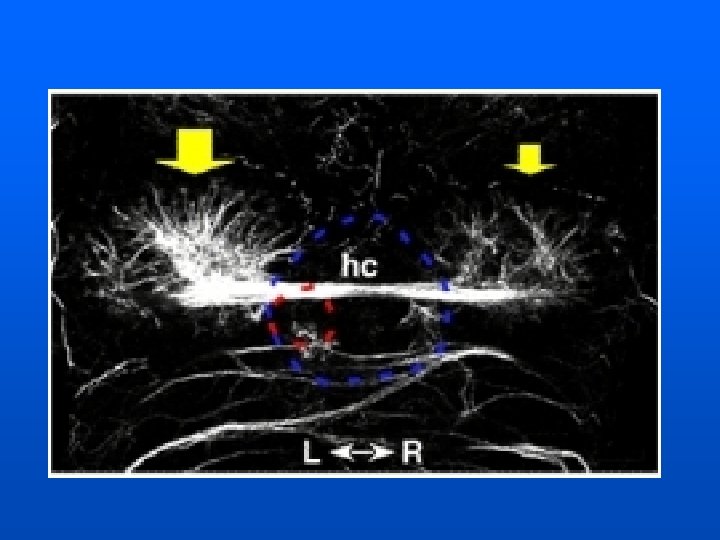

THALAMIC RETICULAR NUCLEUS Cerebral Cortex Thalamic Reticular Nucleus Thalamocortical Neuron Subcortical Structure